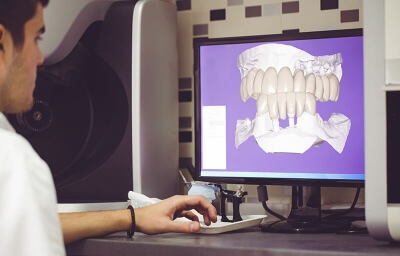

Костно-пластические материалы для имплантологии: подробный обзор

Одномоментная имплантация 13 зуба